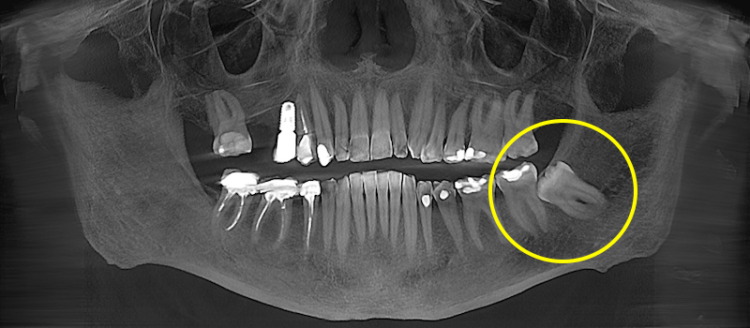

Видалення ретинованого зуба мудрості

Ретинований зуб мудрості — це зуб, який повністю або частково не прорізався й залишається в кістці чи під яснами. Такий зуб може тривалий час не турбувати, але створювати ризик запалення, ураження сусіднього моляра або формування кісти.

Перед видаленням обов’язково оцінюється його положення на рентгені або КТ: глибина залягання, кут нахилу, форма коренів та контакт із нижньощелепним нервом. Це дозволяє спланувати доступ і мінімізувати ризики.

Під час операції формується хірургічний доступ до зуба, за потреби проводиться часткове видалення кістки або розділення зуба на фрагменти для контрольованого вилучення. Після видалення лунка вичищається, промивається й закладається гемостатична губка, накладаються шви.

Відновлення зазвичай триває довше, ніж при простому видаленні, і може супроводжуватися набряком або обмеженням відкривання рота в перші дні.